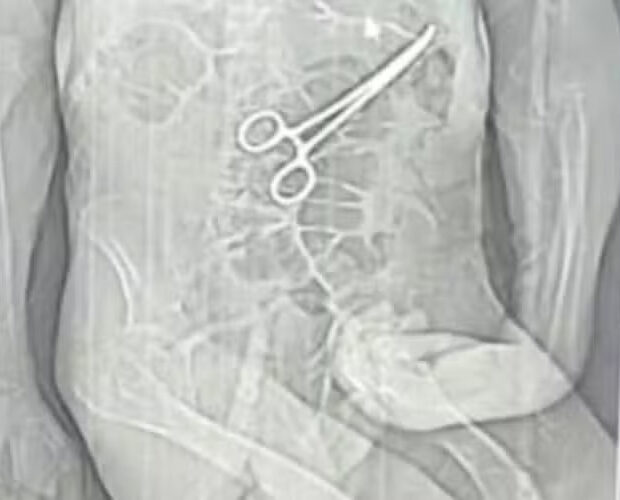

Pinça teria sido esquecida no corpo durante cirurgia; Secretaria de Saúde confirma corpo estranho e abre sindicância

A morte de Manoel Cardoso de Brito, de 68 anos, na véspera do Natal, levantou suspeitas graves sobre a conduta médica no Hospital Municipal Antônio Carneiro Valadares, no Noroeste de Minas Gerais. A família acusa a unidade de saúde de erro médico, alegando que uma pinça cirúrgica teria sido esquecida dentro do corpo do paciente após a primeira cirurgia, fato que só teria sido descoberto depois do óbito.

Manoel morreu no dia 24 de dezembro, um dia antes de completar 69 anos, após passar por dois procedimentos cirúrgicos e permanecer internado por treze dias. Segundo relato dos familiares, a informação sobre o possível esquecimento do instrumento só veio à tona após a divulgação de um exame de tomografia por uma rádio local, o que intensificou a desconfiança sobre a condução do caso.

A Secretaria Municipal de Saúde de João Pinheiro confirmou, em nota oficial, que houve a retirada de um corpo estranho durante a cirurgia. Ao mesmo tempo, informou que o paciente apresentava um quadro clínico grave, com diversas comorbidades. Ainda segundo a pasta, protocolos de segurança foram reforçados e uma sindicância administrativa foi aberta para apurar as circunstâncias da morte.

No dia 11 de dezembro, diante da suspeita de um AVC, foi realizada uma tomografia. Pouco depois, ele foi levado às pressas para uma nova cirurgia. Segundo o boletim, os familiares não foram informados, naquele momento, sobre os motivos do novo procedimento.